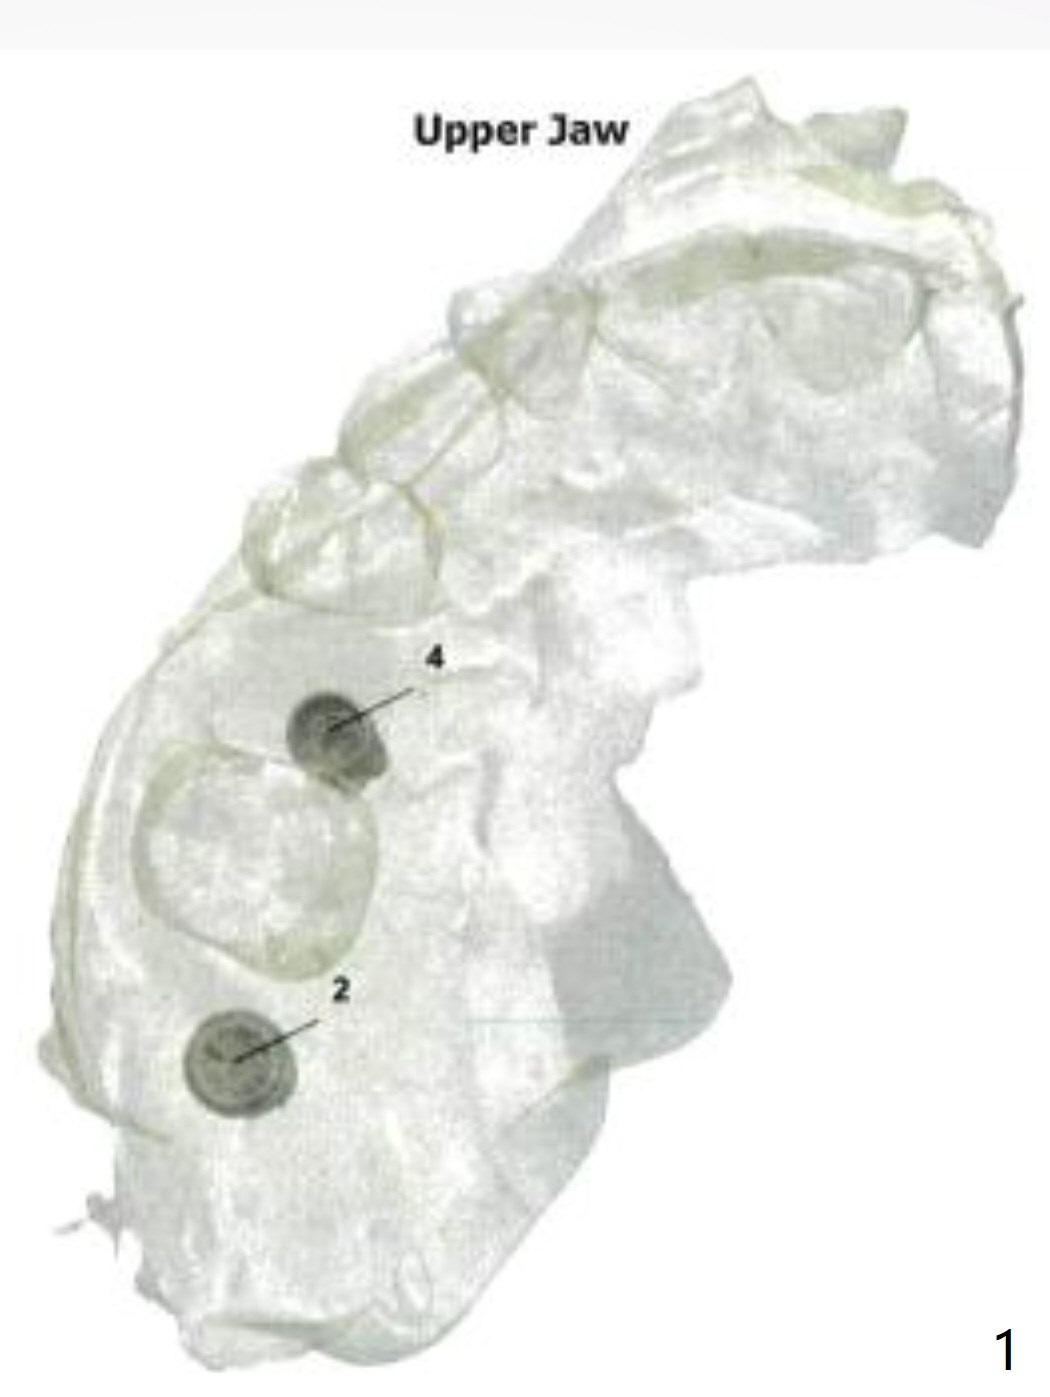

Two Implants

In fact the patient agrees to have 2 implants (#2 and 4) to be placed at the same time.